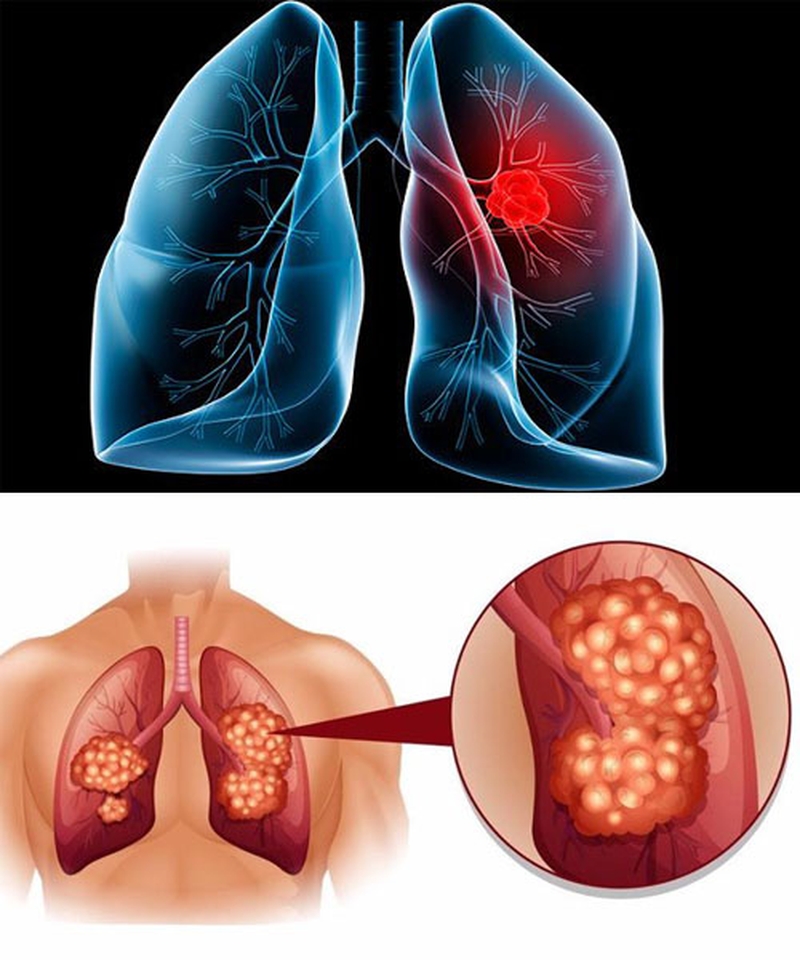

Ung thư phổi là căn bệnh nguy hiểm, tốc độ lây lan cao, những hình ảnh ung thư phổi sẽ khiến nhiều người bàng hoàng, sợ hãi. Chụp phim X-quang nhằm xác định tình trạng bệnh, vậy hình ảnh từ phim X-quang đó có ý nghĩa gì?

Mặc dù hình ảnh các khối u phổi trên phim chụp X quang khá đa dạng, nhưng thường gặp là các khối u mờ (thấy màu sáng trên phim), hình tròn, ranh giới có thể rõ hoặc không. Tùy theo vị trí của khối u sẽ được phân làm 2 loại chính:

• U phổi trung tâm: Đây là các khối u nằm quanh rốn phổi. Trên phim chụp X-quang là khối mờ vùng rốn phổi, bờ tua gai (nham nhở, dạng tia nắng mặt trời), ranh giới không rõ. Do bản chất xuất phát từ các phế quản lớn vùng rốn phổi nên có thể có hình ảnh xẹp thùy phổi của nhánh phế quản u xâm lấn.

• U phổi ngoại vi: Đây là các khối u nằm vùng ngoại vi của lá phổi. U phổi ngoại vi thường có các đặc điểm như hình tròn hoặc bầu dục, bờ và ranh giới rõ.